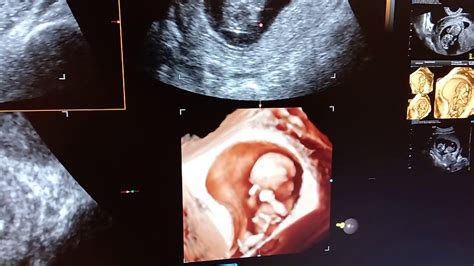

Numele de "Dublu Test" provine de la cele două investigații specifice care se realizează în cadrul acestui screening în primul trimestru, la un interval de timp de maxim 24 de ore: o ecografie morfologică fetală și o analiză de sânge pentru markeri biochimici.

- Date ecografice: vârsta biometrică, mărimea translucenței nucale (spațiul cu lichid din zona cefei fătului) și prezența osului nazal.